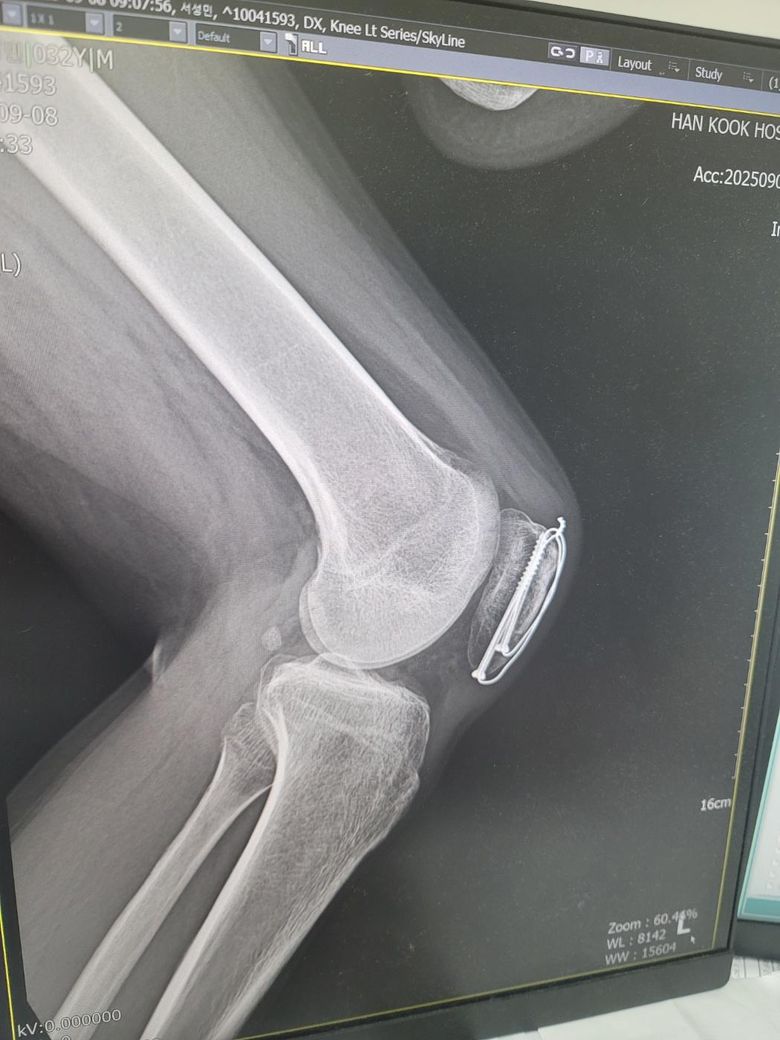

엑스레이 사진은 어제찍은 12주차 사진입니다

1. 엑스레이상 문제는 없나요?

2. 무릎에서 바깥부분부터 가로로 중간부분이 골절선처럼 움푹파여서 만져봐도 움푹파여있던데 뼈가 녹았다거나 생기다가 말수도 있는건가요? 참고로 분쇄골절입니다 ㅠㅠ

사진상으로 12주차라면 분쇄골절 회복 중인 상태로 보이고 금속 고정장치가 잘 자리 잡혀 있는 것으로 확인되어 보여요

무릎 바깥쪽 움푹 패인 부분은 골절 부위의 골융합이 아직 완전히 진행되지 않아 나타나는 정상 회복과정일 수 있습니다.

뼈가 녹았다기보다는 아직 뼈가 재형성중이거나 골편 사이가 완전히 매워지지 않은 상태로 볼 수 있습니다!

사진상 정확한 상태 파악이 어려울 수도 있지만 금속 핀 고정은 유지되어 있으며 골절 편들이 비교적 잘 맞춰져 있는 것으로 보입니다. 분쇄골절의 경우 뼈가 완전히 붙는 데 시간이 오래 걸리며 12주차 라면 아직 골소주들이 선명하게 연결되지 않은 상태로 특별한 핀 이탈이나 심한 전위가 없다면 큰 문제는 없을 것으로 생각됩니다.

무릎 중간 부분이 움푹 패여 보이는 것은 수술 후 연부조직의 위축 때문에 패여 보일 수 있으며 골절 부위의 고나절면이 함몰된 경우에도 패임이 느껴질 수 있습니다. 뼈가 녹았다기보다는 골절 치유 과정에서 흡수 재형성이 일어나거나 관절 연골의 손상 때문에 패여 보일 가능성이 있다고 생각합니다.